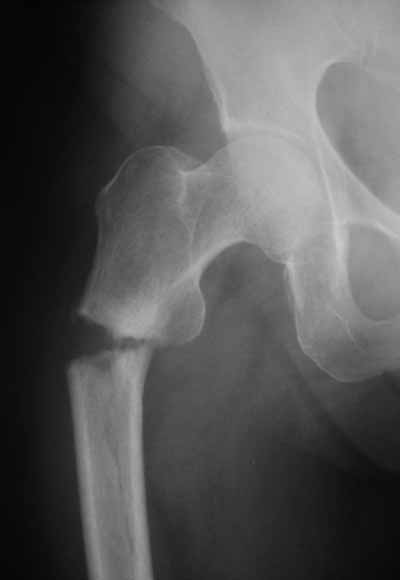

Да? Качество рентгенограмм конечно неочень, но ведь это нестабильный перелом 31.А2.2, не так ли?

Не думаю так. см вложение.

> Да? Качество рентгенограмм конечно неочень, но ведь это

> нестабильный перелом 31.А2.2, не так ли?

Ну, после помещения туда такого гвоздя даже без дистального винта заметной нестабильности уже не остается ;-)